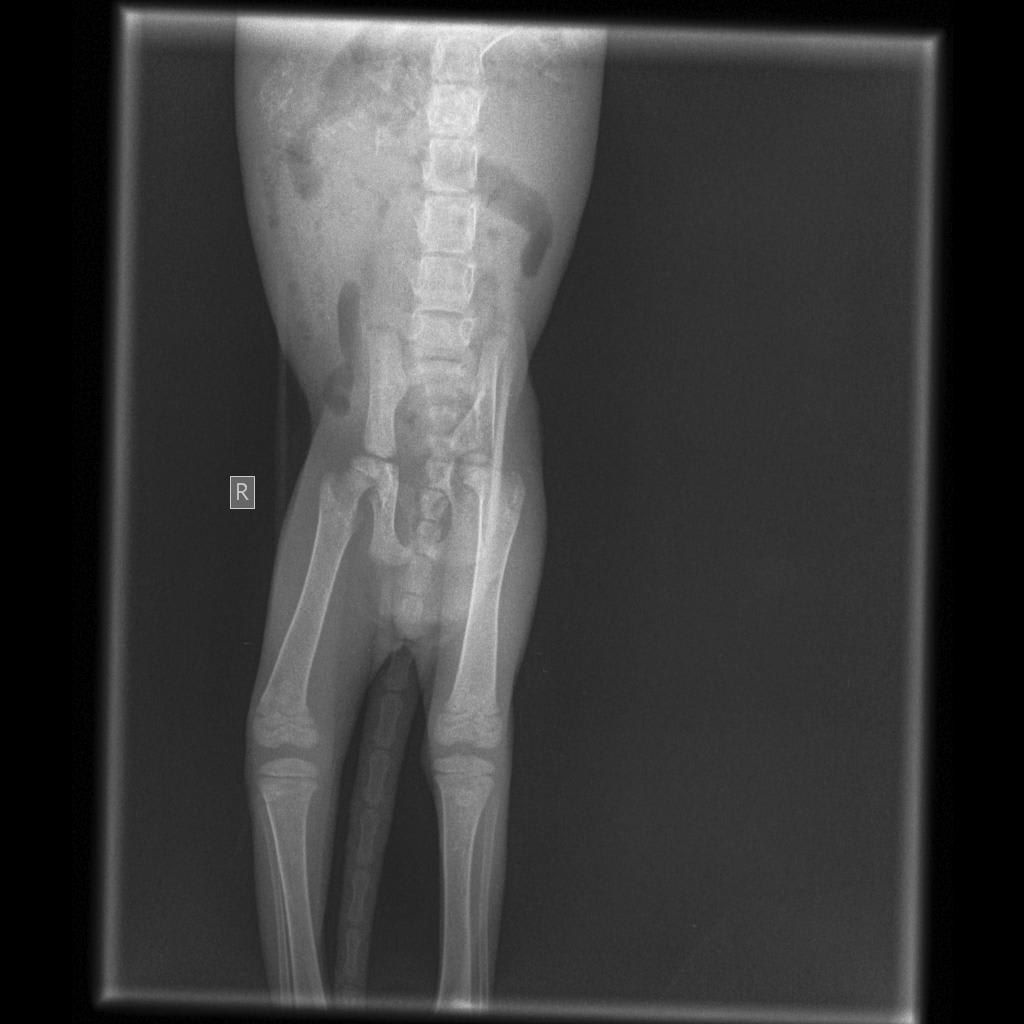

On 13th 2am-3am i hear my kitten screaming from my front gate and and saw her flopping on the ground in pain. I rushed to pick her up and laided her on my lap making her calmed. I stayed awake all night because my kitten will immediately start flopping in pain again. Has brought her to the vet in the evening and the did an xray scan. The vet told me that my kitten left pelvis bone is fractured. But her is limping on her back right leg. The vet said the is nothing much can do to a kitten

In your x-ray I do see the broken pelvis and it looks like it is left sided based on the markers on the x-ray. I'm surprised that she would be putting weight on her left leg, but it's possible that she has another injury that wouldn't be apparent on the x-ray or that the x-ray was mislabeled if this is the case. I would recommend calling or rechecking with the vet - they might want to repeat an x-ray to see if things have changed and if there is something wrong on the other side of her pelvis and leg.